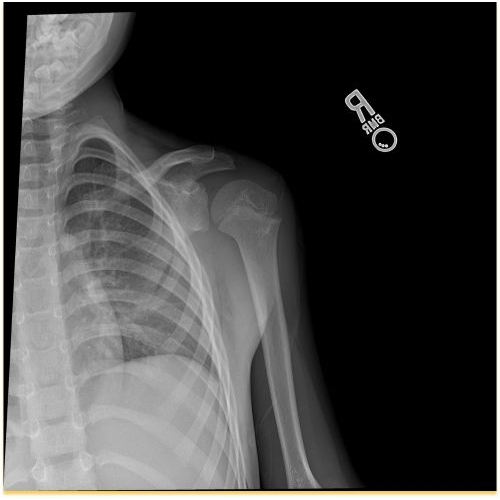

| Monkey Bar Mishap: A Unique Scapulothoracic Injury And Presentation - Page #3 | |||